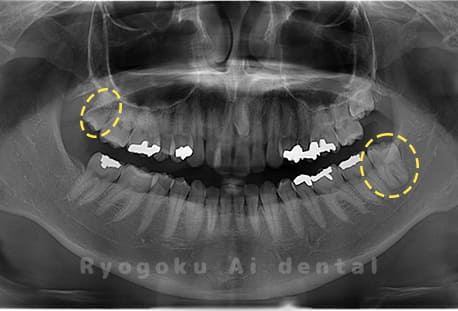

Case03

-

- 原因

- 上顎、下顎の親知らず

- 治療内容

- 上下4本の親知らずを抜歯したケースです。

<リスク・副作用>

手術後は痛み、腫れ、痺れなどの副作用が生じる場合があります。